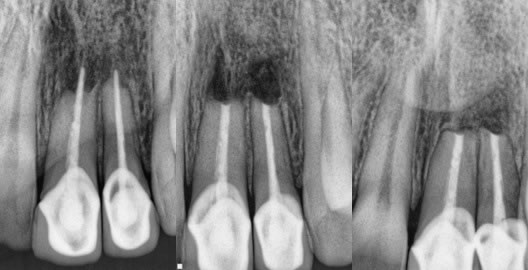

3. Extreme conditions of calcification that made perfect root canal treatment impossible. (figures 9,10,11)

Figures 9,10,11: pre-op / post-op / 1.5 year recall

Original root canal effort done by a highly skilled endodontist who could not find the extremely calcified canal and the post/crown complex was very esthetic. Patient did not want it removed and thus I performed the apicoectomy with a very nice result.